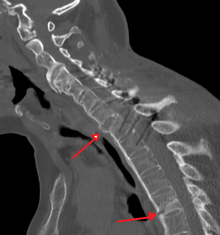

There is no direct test to diagnose AS. The Schober's test is a useful clinical measure of flexion of the lumbar spine performed during the physical examination.[11] Magnetic resonance imaging (MRI), and X-ray studies of the spine, which show characteristic spinal changes and inflammation of the sacroiliac joint, combined with a genetic marker blood test are the major diagnostic tools.

Radiographic features

- The earliest changes in the sacroiliac joints demonstrable by plain x–ray shows erosions and sclerosis.

- Progression of the erosions leads to pseudo-widening of the joint space and bony ankylosis.

- X-ray spine can reveal squaring of vertebrae with spine ossification with fibrous band run longitudinally called syndesmophyte while producing bamboo spine appearance.

- A drawback of X-ray diagnosis is the signs and symptoms of AS have usually been established as long as 8–10 years prior to X-ray-evident changes occurring on a plain film X-ray, which means a delay of as long as 10 years before adequate therapies can be introduced. Options for earlier diagnosis are tomography and MRI of the sacroiliac joints, but the reliability of these tests is still unclear.

CT scan showing Bamboo spine in ankylosing spondylitis